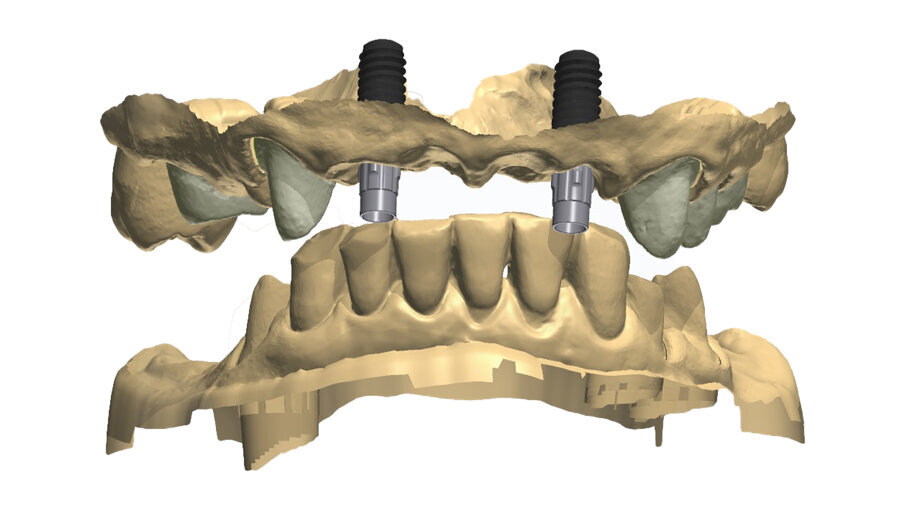

- Fase 2 - pianificazione implantare: sono stati posizionati impianti della medesima casa implantare ma con caratteristiche diverse al fine di esaltare al massimo la loro peculiarità sia in zona estetica che in zona funzionale inferiore con tipologie TL (RN 4.1 e TE 4.1 Straumann) e BL (BLT 4.1 Straumann) per una corretta protesizzazione avvitata e cementata.

- Fase 3 - chirurgia: nel sestante frontale superiore dove era richiesta una maggior attenzione sia per la quantità di osso residuo che per un posizionamento ineccepibile associato a rigenerazione ossea è stata progettata e seguita una chirurgia guidata mediante l’uso di un software (coDiagnostiX, Straumann) dedicato alla chirurgia computer assistita statica.

Per un’analisi completa in casi così compromessi è necessario il maggior numero di informazioni che dovranno essere raccolte partendo dal confronto con la paziente per quelle che sono le abitudini alimentari, la sua attività lavorativa, gli interessi sociali. Tutto ciò permette di capire quanto la paziente si aspetti dal nostro intervento ponendo la giusta attenzione all’estetica oltre che alla naturale funzione, è altresì importante rilevare delle immagini con e senza la protesi provvisoria in situ (Fig. 2). Nonostante si evinca la mancanza di congruità del manufatto protesico con la cresta residua la paziente ha mostrato difficoltà nel concepire una sua sostituzione per il timore di un peggioramento estetico. Il supporto di un progetto digitale ha consentito alla paziente di capire quale risultato potesse raggiungere a percorso ultimato. È evidente il collasso che il labbro superiore subisce quando viene rimossa la protesi con la rappresentazione del “codice a barra” dato dalla mancanza dei denti e della struttura ossea sottostante (Figg. 3, 4), a tal scopo è consigliabile poter fotografare la paziente nel profilo in entrambe le situazioni così da far emergere le discrepanze, anche nell’impronta digitale rilevata è importante acquisire il maggior numero di informazioni (Fig. 5). L’informazione diagnostica dettagliata è fornita dalla CBCT, pertanto abbiamo pianificato la sua esecuzione dopo la prima provvisorizzazione dell’arcata superiore evitando lo scattering da metalli presenti. Il file STL del wax-up (Fig. 6) associato al file STL dell’impronta senza provvisorio (Fig. 7) e al file DICOM radiologico (Figg. 8, 9) ha permesso una corretta progettazione chirurgico implantare (Fig. 10) nel rispetto della porzione ossea della cresta residua, ottimizzando la conseguente realizzazione della dima chirurgica (Fig. 11) per il posizionamento degli impianti in sede 1.2 e 2.2 (Figg. 12-14) anche nel rispetto della posizione degli elementi in antagonismo (Fig. 15).

Fig. 15_Nella visione di centrica è possibile valorizzare il progetto di posizionamento che ha tenuto conto della disponibilità ossea per sfruttare al massimo l’osso nativo, la posizione degli incisivi laterali, il parallelismo implantare il foro di fissaggio all’interno del cingolo coronale per non compromettere la porzione estetica vestibolare.